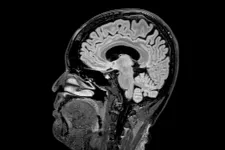

Korszakai vannak az agyunknak, és a felnőttkort 30 év alatt el sem éri

Egy friss kutatás szerint az agyi fejlődés öt különböző érába sorolható, és mindegyikben más változások a legjellemzőbbek.